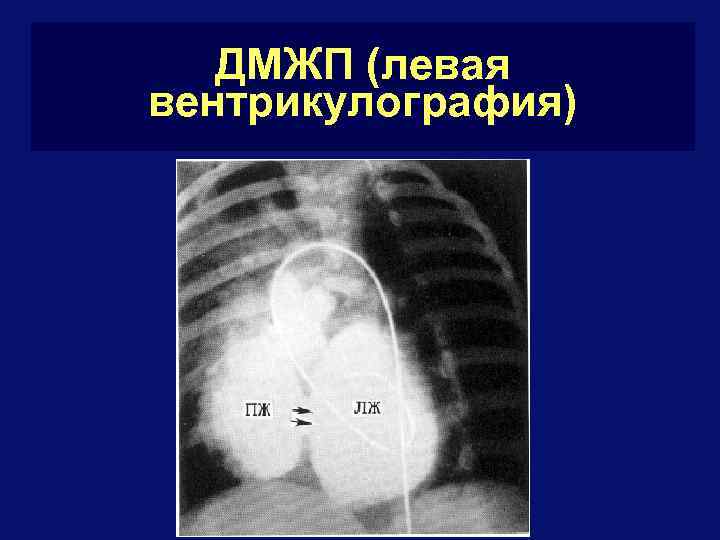

ДМЖП (левая вентрикулография)